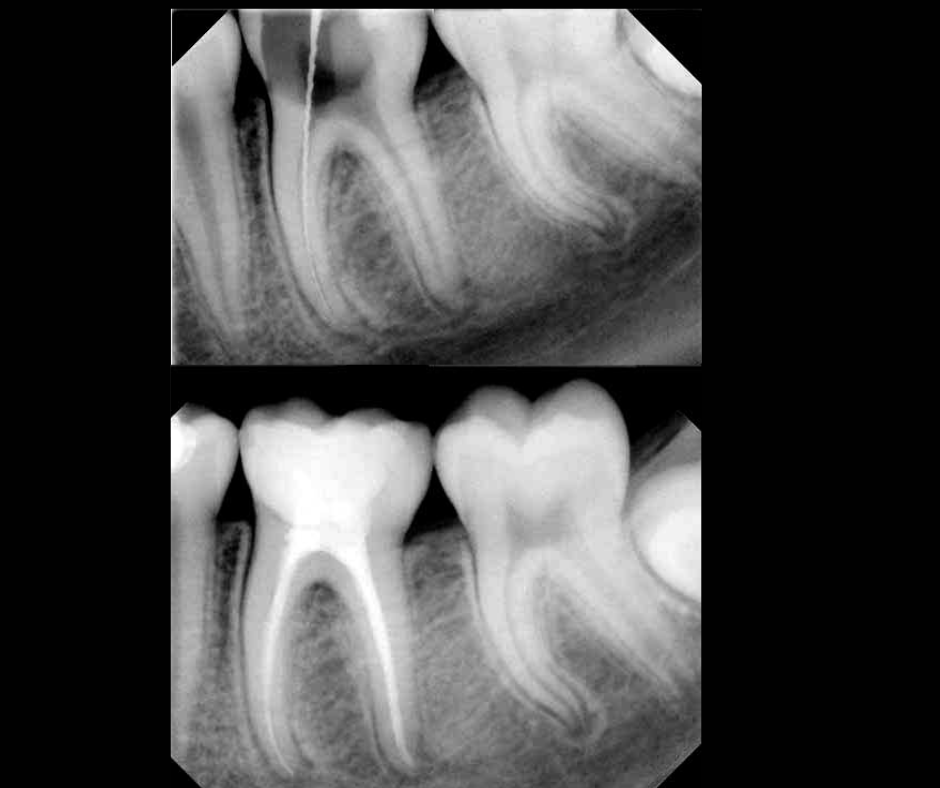

La endodoncia —conocida como “tratamiento de conducto”— es un procedimiento que permite salvar un diente afectado por infección, dolor o daño profundo.

¿Cuándo necesitas una endodoncia?

Recomendamos una valoración cuando presentas:

Caries profunda

Infección o inflamación